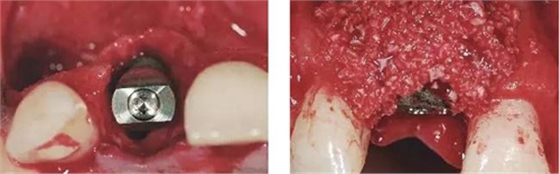

圖6、從磨牙后區(qū)用環(huán)形鉆獲取自體骨,并將其放置在種植體的表面。Geistlich Bio-Oss®骨顆?;旌涎悍胖迷谧泽w骨的外側(cè),防止自體骨的早期吸收。植骨可以穩(wěn)定軟組織外形。

圖7、植骨區(qū)外覆蓋Geistlich Bio-Gide®雙層膠原膜,使得植骨區(qū)更為穩(wěn)定。